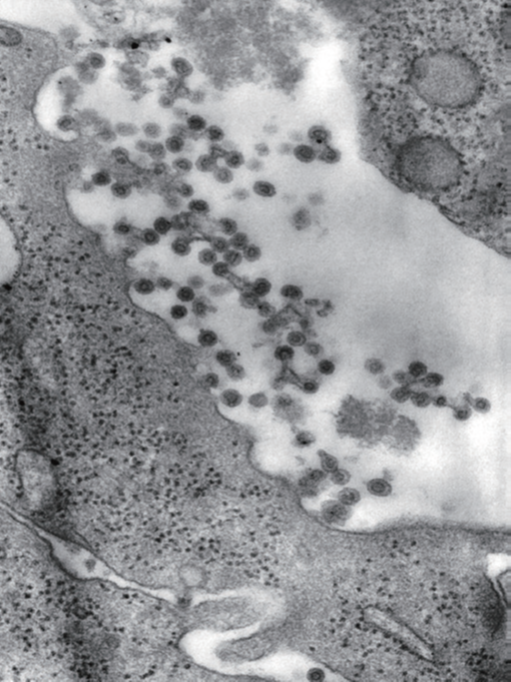

麻疹病毒

(CDC / Cynthia S. Goldsmith)